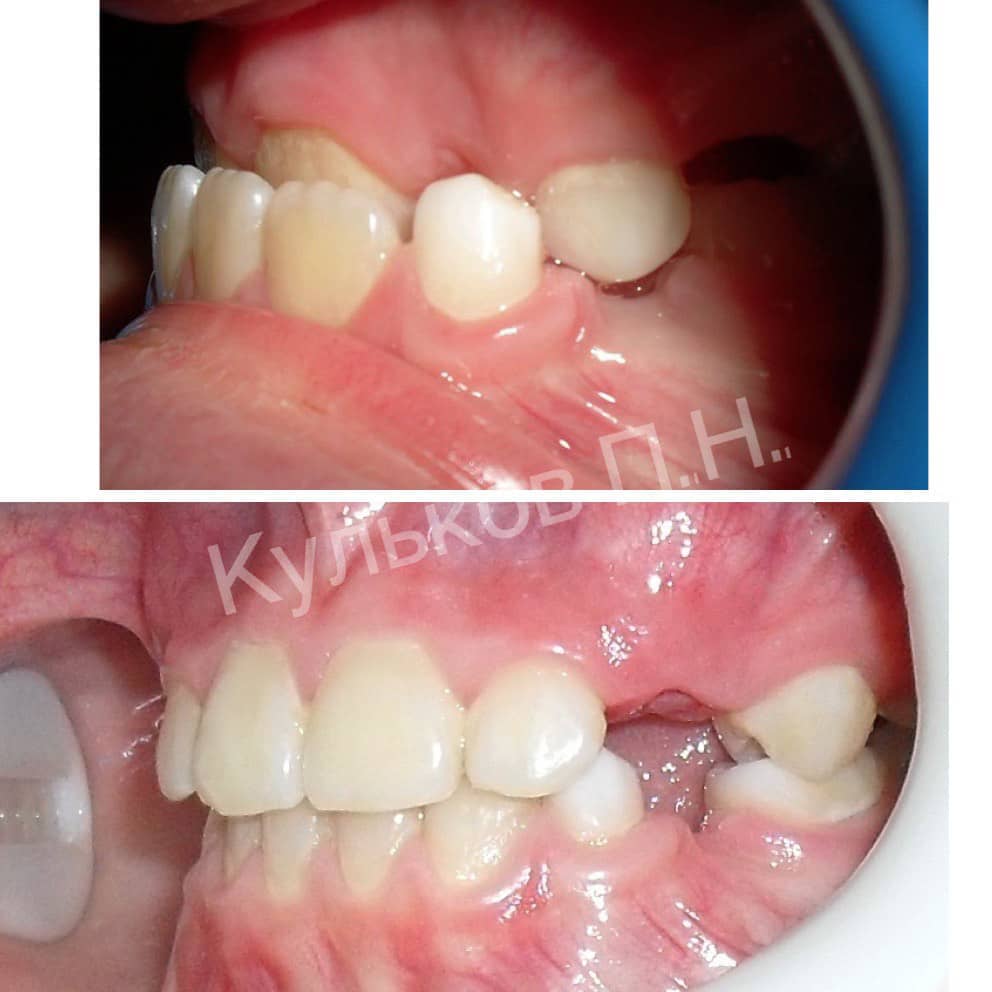

Пациент 8 лет.

Врач: Кульков Павел Николаевич

Диагноз: сменный прикус, мезиальный прикус с глубоким обратным резцовым перекрытием. Ранняя потеря молочных зубов.

Лечение: разобщающая пластинка на нижнюю челюсть.

Срок ношения: 8 месяцев.